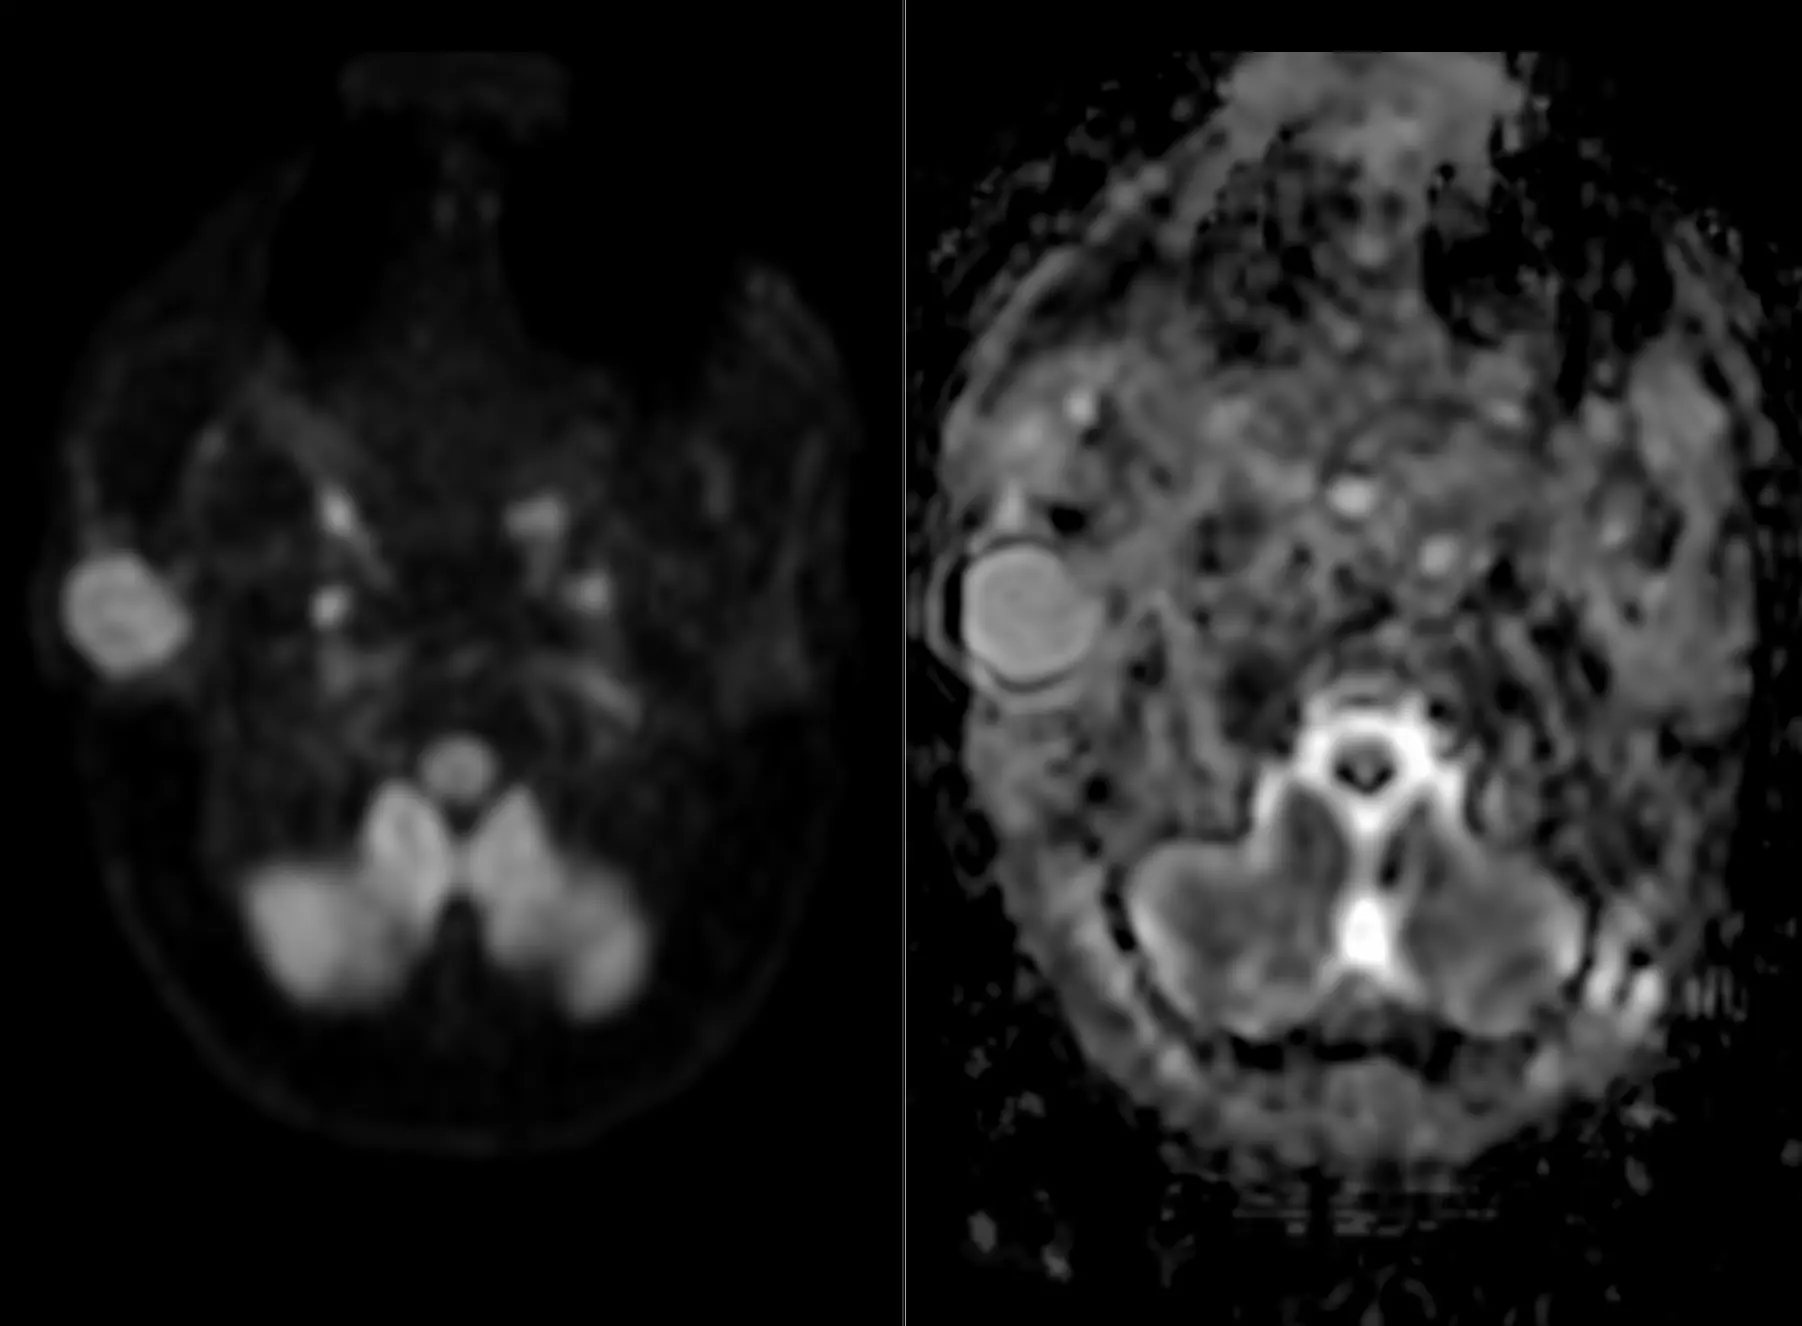

Мужчина 35 лет, месяц назад упал с высоты двух метров, сейчас не полностью ориентирован в месте и времени. Типичная (кроме мозжечка справа) картина травматического аксонального повреждения 3 степени (с поражением ствола). Множественные мелкие точечные и линейные микрокровоизлияния, вокруг части из них видны глиоз/отек. А вот в мозжечке, реально, нечасто такое увидишь. Но бывает. Типа, как вот здесь: